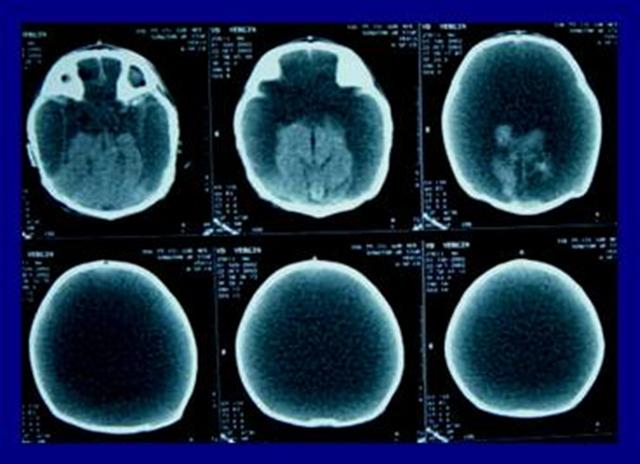

Bıngıldağı açık bebeklerde kafa ultrasonografisi tanı konmasında ucuz bir yöntemdir. Bilgisayarlı beyin tomografisi (Resim 1) veya manyetik rezonans görüntüleme beyin dokusunun kaybını göstermede yeterlidir.

Resim 1: Bilgisayarlı beyin tomografisinde sadece beyin sapı ve beyincik izlenmekte, beyin yarı-kürelerinin kaybolduğu ve yerini BOS’un doldurduğu görülmektedir. Bu görüntü hidranensefali için tipiktir.